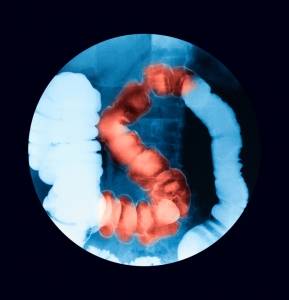

Fluoroscopy is a special type of x ray imaging used for many types of imaging studies such as esophograms, upper GI series, barium enemas, cystograms and hystersalpingograms. Fluoroscopy can also be used to guide procedures such as arthrograms/joint injections, lumbar punctures and myelograms, and many others.